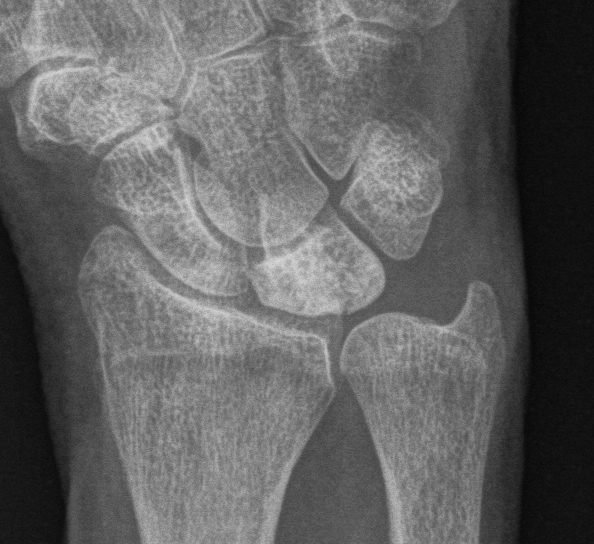

| Stage IIIB | Stage IV |

|---|---|

|

Collapse / fragmentation Scaphoid flexed / Capitate migrates proximally |

Pancarpal osteoarthritis |

![]() |